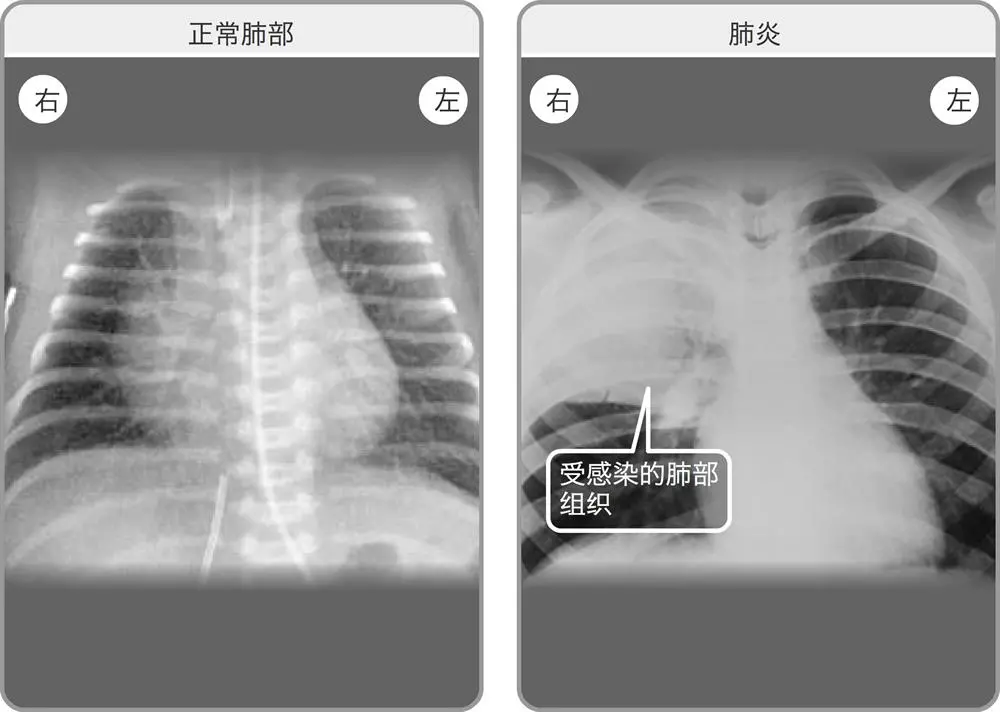

“白肺”,这个经常出现在“新冠肺炎”疫情中的词语,其实这个是指在X光检查下肺部显影呈大片白色状。出现“白肺”,一般意味着肺部有严重感染。

其实,新型冠状病毒肺炎的患者胸部CT或胸片不都是“白肺”,在患病初期,双肺的CT显示正常,但随着疾病发展,若没有得到治疗,肺部便会出现病变加重,也就是俗称“磨玻璃”影。

人的肺就像是二个气囊,在X线下照射,因为密度低,X光穿透性较好,所以在片子上显示是黑色的,“白肺”则是肺部出现严重感染后,肺部充血,渗出及炎性细胞浸润,

密度变高,这才导致双肺X光穿透性较差。